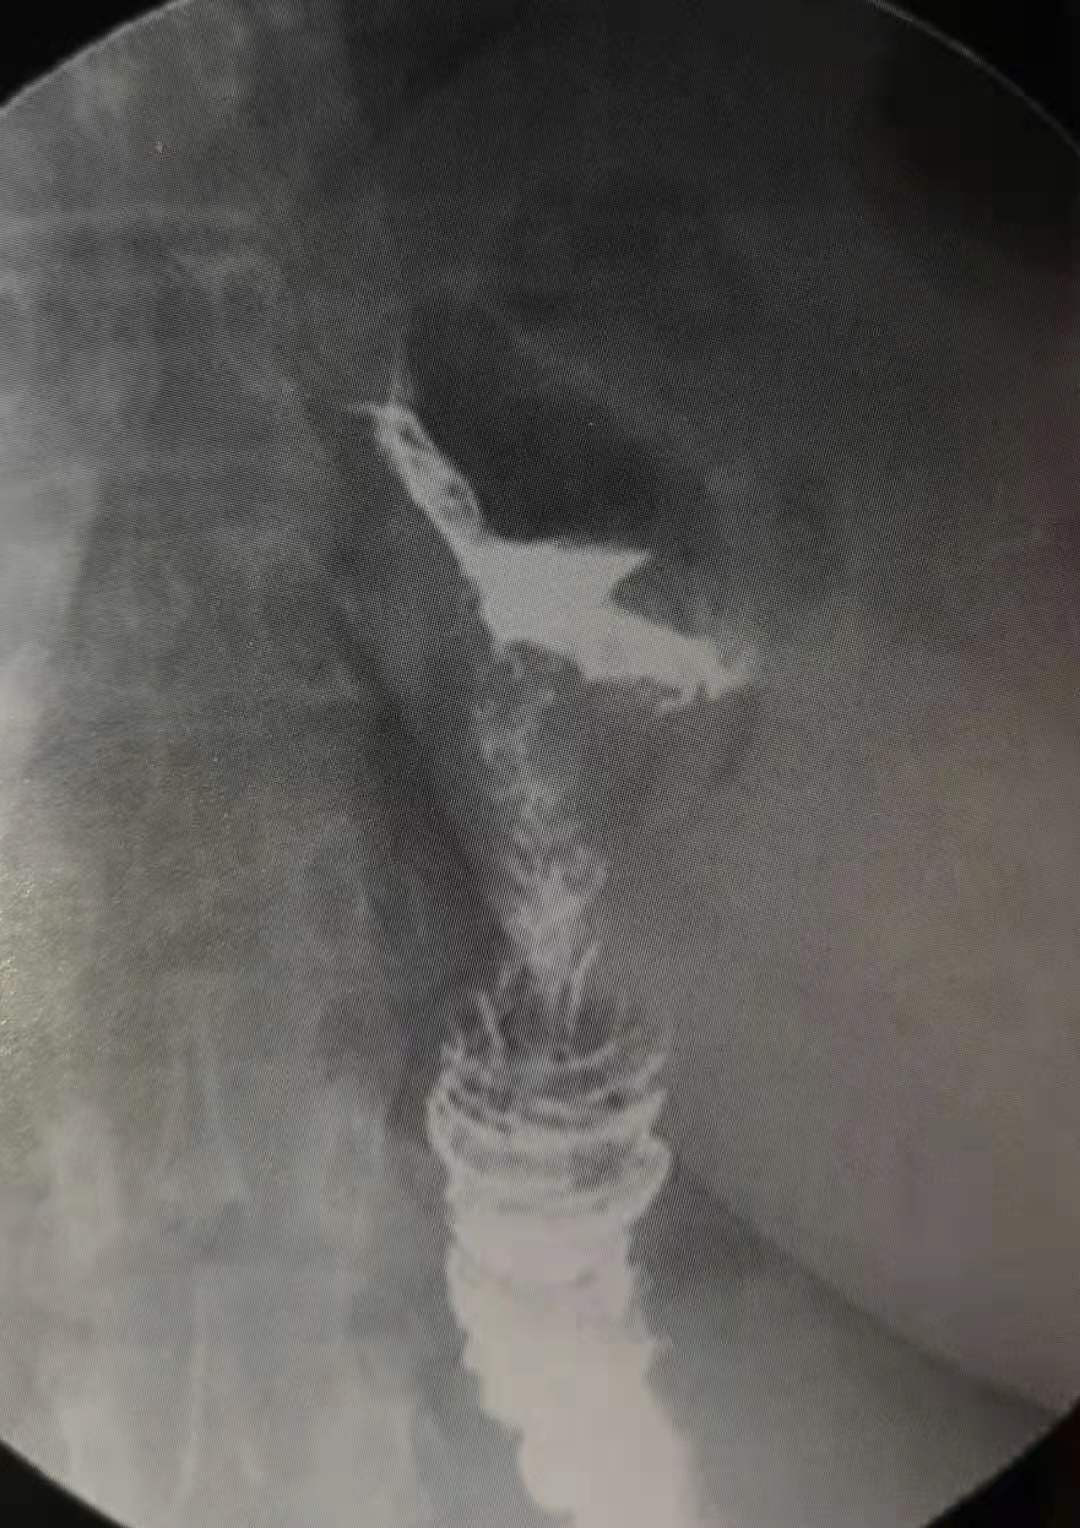

这位36岁的女士,就是手术后发生了胃束带移位,引起梗阻,恶性呕吐入院。

据报道,这种情况发生概率约为4-13%,严重时可以发生胃缺血坏死。